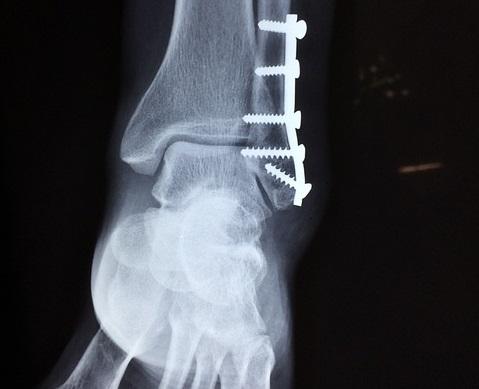

Estudo analisou os fatores de risco associados à infecção relacionada à fratura em pacientes submetidos à cirurgia de tornozelo.